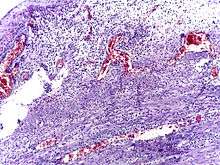

Micrograph of appendicitis and periappendicitis. H&E stain.

Micrograph of appendicitis showing neutrophils in the muscularis propria. H&E stain.

The definitive diagnosis is based on pathology. The histologic finding of appendicitis is neutrophilic infiltrate of the muscularis propria.

Periappendicits, inflammation of tissues around the appendix, is often found in conjunction with other abdominal pathology.[56]